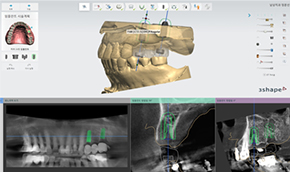

3D 디지털 모의수술을 통한

임플란트 과정을 미리보다3D CT 분석을 통한 검진 결과를 바탕으로 환자 맞춤형 가이드를 미리 제작합니다. 이후 3D 컴퓨터 모의수술을 통해 경로를 결정하고 소량 절개 시술로 잇몸 손상과 통증을 줄입니다. 오차는 줄이고 정확성은 높힌 디지털 임플란트 입니다.

골조직, 신경위치 자세히 분석 가능

최적의 임플란트 위치 선정 가능

빠르고 편리한 진료 과정

출혈, 통증, 붓기가 적은 최소 절개 시술로 빠른 회복